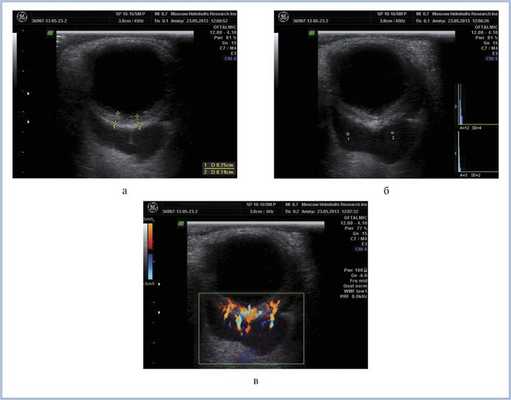

КТ позволила выявить ретробульбарную ткань с достаточно четкими границами, локализующуюся вокруг зрительного нерва, а также утолщение хориоидеи слева (рис. 4). Патологических изменений справа по данным КТ выявлено не было. С помощью УЗДС слева в В-режиме непосредственно за задним полюсом глаза (вокруг зрительного нерва) определяли гипоэхогенную, практически однородную опухолевую ткань с четкими неровными контурами. Одновременно выявили диффузное утолщение хориоидального слоя в области заднего полюса глаза — до 2,5 мм (рис. 5, а). Ультразвуковой денситометрический анализ, проведенный на основе двумерных серошкальных гистограмм, продемонстрировал крайне низкие значения акустической плотности ткани (А=3—12 усл. ед.) (см. рис. 5, б). В режиме цветового допплеровского картирования (ЦДК) отмечена гиперваскуляризация ретробульбарного и интраокулярных очагов с высокими линейными характеристиками кровотока. Следует отметить, что два указанных процесса — внутриглазной и орбитальный имели единую васкуляризацию (см. рис. 5, в). Патологических изменений в правом глазу по данным ультразвукового исследования выявлено не было.

Рис. 5. Результаты дуплексного сканирования. а — утолщение хориоидеи; б — денситометрические показатели акустической плотности опухоли в В-режиме; в — множественные собственные сосуды опухоли, единая васкуляризация внутриглазного и орбитального очагов в режиме ЦДК.